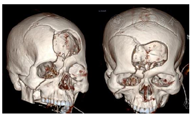

头颅CT(图1)提示:双侧额叶脑挫裂伤并出血术后状态;颅骨CT三维成像(图2)提示:额骨骨质缺损,额窦壁、右侧眼眶内壁、上颌窦壁等多处骨折。脑脊液检查结果:葡萄糖<1.0 mmol/L,乳酸5.62 mmol/L,氯106.7 mmol/L,蛋白质1.19 mmol/L,白细胞计数(white blood cell count,WBC)83×106/L。